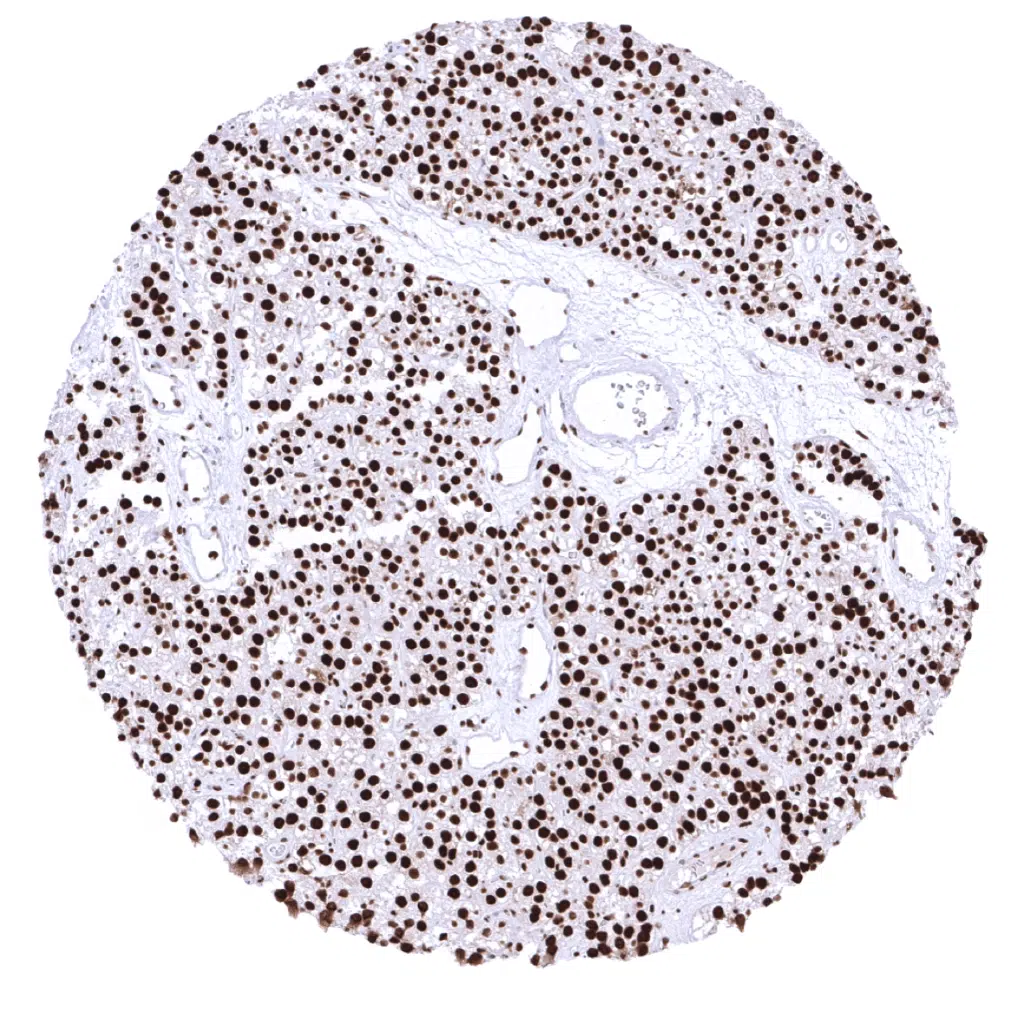

Testis